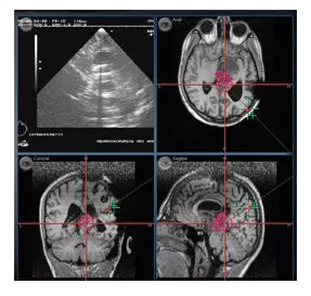

Hastanın saçlı derisine, yüzey belirleyicileri veya lazer işaretleri kullanımı ile baş ve yüzün topografik anotomisi çıkarılmaktadır. Elde edilen veriler beyindeki hastalığın BT veya MR görüntüleri kullanılan bilgisayar yardımıyla planlanması yapılmaktadır. Sanal ortamda planlanan görüntülerin, gerçek ortama yansımasında saçlı deri kesisi, kemik pencere kaldırılması ve daha önemlisi beyin içerisinde varılacak hedef, 3 boyutlu olarak seçilmektedir.

Bu planlama ve sanal işlem beyin ameliyatı yapılacak bölgeye ulaşmada büyük katkılar sağlamaktadır. Örneğin, ulaşılacak beyin hedefine en kısa, en doğru ve en emin yol seçilmektedir. Bu teknolojiyle kullanılarak yapılan beyin ameliyatının hastadaki kazanımları; daha az hastanede kalma, daha az kan kullanılması, daha kısa ameliyat süresi, en önemlisi de daha erken gündelik hayata dönebilmesidir. Diğer bir önemli avantajlar ise, beyindeki tümöre ulaşmada beyin dokusuna zarar vermede minimal riski olması ve cerrahın tümörü tamamınını çıkarılıp çıkarılmayacağı konsunu anlamada yardımcı olmasıdır.

Optimal ameliyat için tümör ile çevre beyin anotomisi üç boyutlu görüntülenmektedir.

Beyindeki tümorün total olarak çıkarılıp çıkarılmadığı 3 boyutlu olarak anlaşılmaktadır.